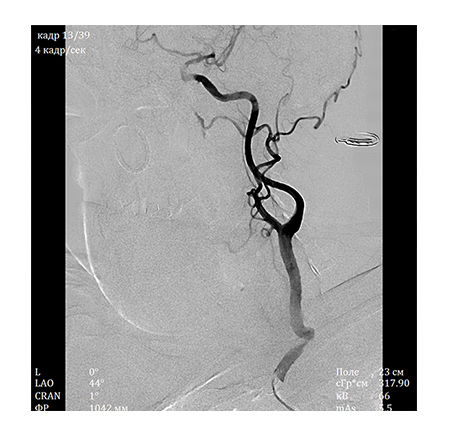

The X-ray angiography system developed by NIPK Electron Co. is a versatile system, which allows performing a wide range of diagnostic procedures:• Angiography of the brain and cervical vessels

A special value of the angiography system consists in high information content of the obtained image. A unique imaging system based on a flat panel detector with spatial resolution of 50 μm, which is superior to foreign analogs regarding its specifications, ensures high diagnostic imaging quality. The examinations allow not only to obtain information about the functional state of the vessels and reveal the signs of disorders but also help determine the accurate localization and seriousness of the revealed abnormality using special calculation packages.

• Digital subtraction angiography (DSA) with choice of subtraction level (Landmark)

• Road Map function for convoluted and difficult to pass parts of a vessel